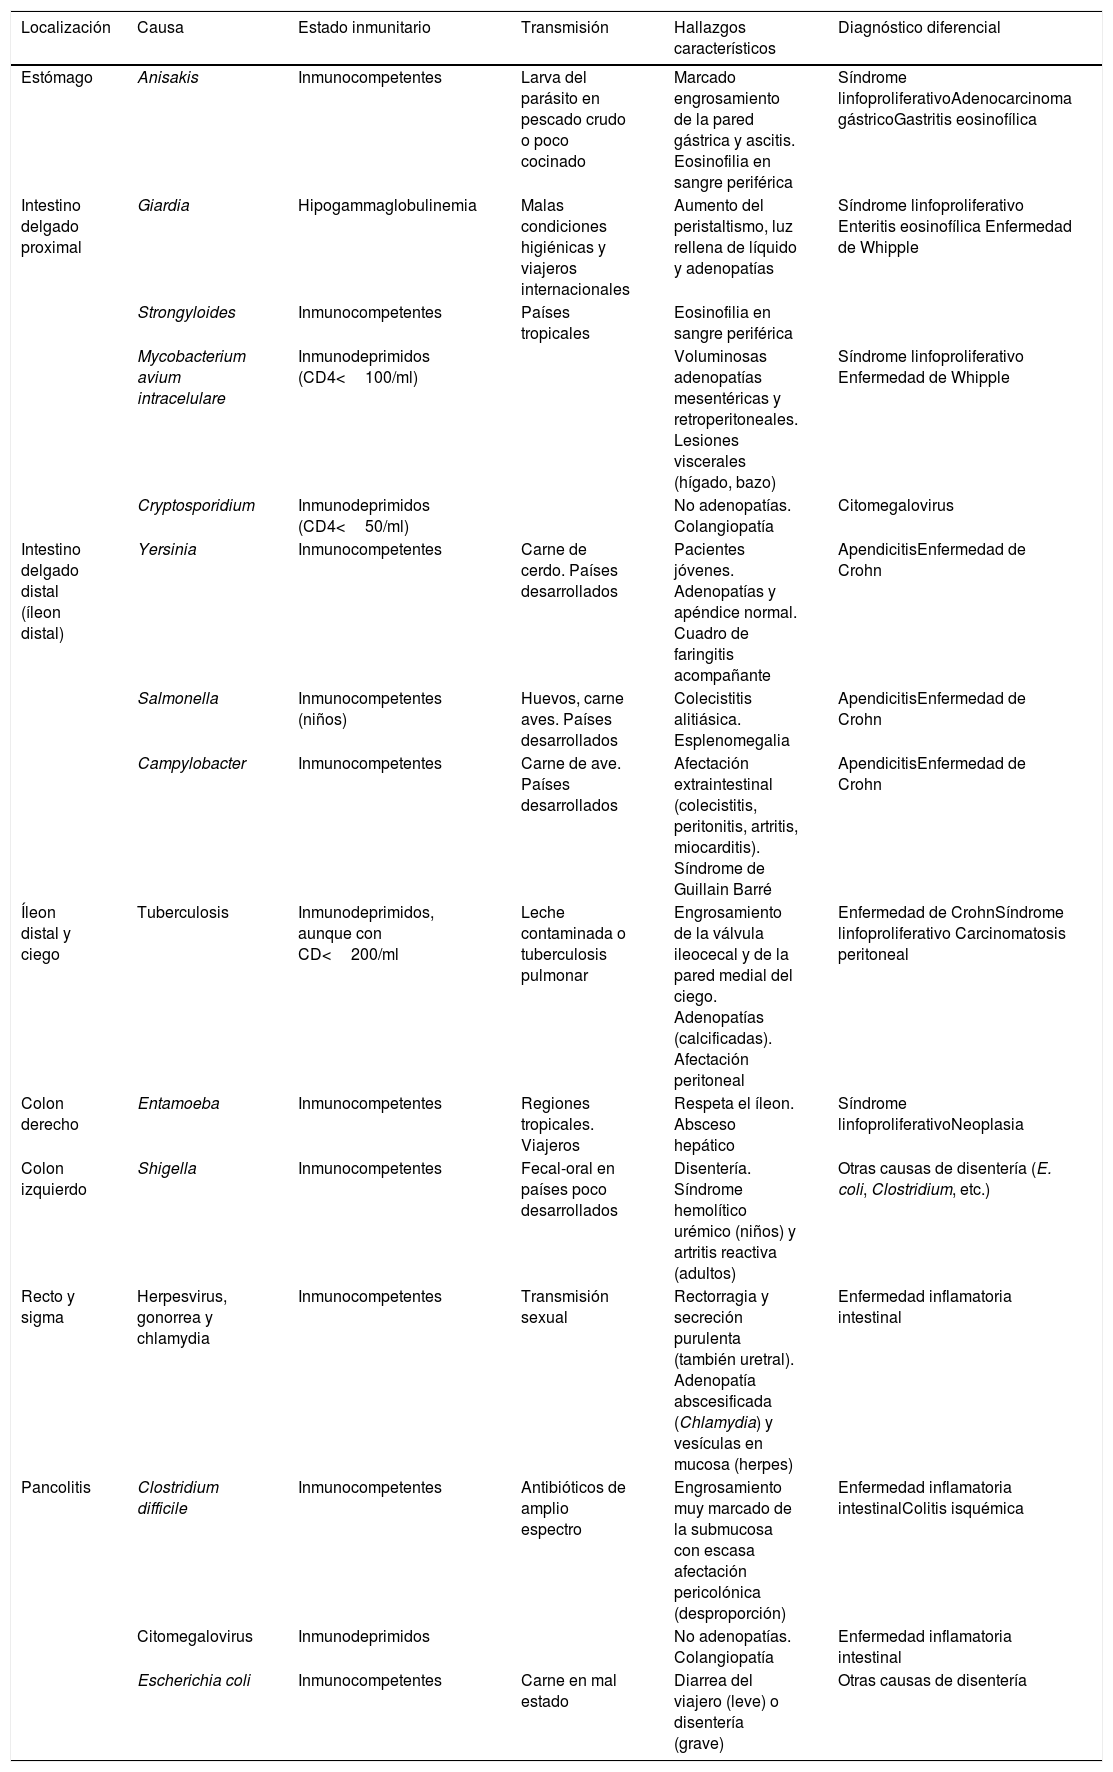

Estos hallazgos son inespecíficos y no permiten establecer un diagnóstico etiológico definitivo, pero algunas características, como la distribución de la afectación, el estado inmunitario del paciente y la presencia de manifestaciones extraintestinales, permiten orientar el posible origen del cuadro. Presentamos algunas de las causas más frecuentes en nuestro medio, siguiendo un esquema topográfico, que se resumen en la tabla 1.

Resumen de infecciones del tracto gastrointestinal

| Localización | Causa | Estado inmunitario | Transmisión | Hallazgos característicos | Diagnóstico diferencial |

|---|---|---|---|---|---|

| Estómago | Anisakis | Inmunocompetentes | Larva del parásito en pescado crudo o poco cocinado | Marcado engrosamiento de la pared gástrica y ascitis. Eosinofilia en sangre periférica | Síndrome linfoproliferativoAdenocarcinoma gástricoGastritis eosinofílica |

| Intestino delgado proximal | Giardia | Hipogammaglobulinemia | Malas condiciones higiénicas y viajeros internacionales | Aumento del peristaltismo, luz rellena de líquido y adenopatías | Síndrome linfoproliferativo Enteritis eosinofílica Enfermedad de Whipple |

| Strongyloides | Inmunocompetentes | Países tropicales | Eosinofilia en sangre periférica | ||

| Mycobacterium avium intracelulare | Inmunodeprimidos (CD4<100/ml) | Voluminosas adenopatías mesentéricas y retroperitoneales. Lesiones viscerales (hígado, bazo) | Síndrome linfoproliferativo Enfermedad de Whipple | ||

| Cryptosporidium | Inmunodeprimidos (CD4<50/ml) | No adenopatías. Colangiopatía | Citomegalovirus | ||

| Intestino delgado distal (íleon distal) | Yersinia | Inmunocompetentes | Carne de cerdo. Países desarrollados | Pacientes jóvenes. Adenopatías y apéndice normal. Cuadro de faringitis acompañante | ApendicitisEnfermedad de Crohn |

| Salmonella | Inmunocompetentes (niños) | Huevos, carne aves. Países desarrollados | Colecistitis alitiásica. Esplenomegalia | ApendicitisEnfermedad de Crohn | |

| Campylobacter | Inmunocompetentes | Carne de ave. Países desarrollados | Afectación extraintestinal (colecistitis, peritonitis, artritis, miocarditis). Síndrome de Guillain Barré | ApendicitisEnfermedad de Crohn | |

| Íleon distal y ciego | Tuberculosis | Inmunodeprimidos, aunque con CD<200/ml | Leche contaminada o tuberculosis pulmonar | Engrosamiento de la válvula ileocecal y de la pared medial del ciego. Adenopatías (calcificadas). Afectación peritoneal | Enfermedad de CrohnSíndrome linfoproliferativo Carcinomatosis peritoneal |

| Colon derecho | Entamoeba | Inmunocompetentes | Regiones tropicales. Viajeros | Respeta el íleon. Absceso hepático | Síndrome linfoproliferativoNeoplasia |

| Colon izquierdo | Shigella | Inmunocompetentes | Fecal-oral en países poco desarrollados | Disentería. Síndrome hemolítico urémico (niños) y artritis reactiva (adultos) | Otras causas de disentería (E. coli, Clostridium, etc.) |

| Recto y sigma | Herpesvirus, gonorrea y chlamydia | Inmunocompetentes | Transmisión sexual | Rectorragia y secreción purulenta (también uretral). Adenopatía abscesificada (Chlamydia) y vesículas en mucosa (herpes) | Enfermedad inflamatoria intestinal |

| Pancolitis | Clostridium difficile | Inmunocompetentes | Antibióticos de amplio espectro | Engrosamiento muy marcado de la submucosa con escasa afectación pericolónica (desproporción) | Enfermedad inflamatoria intestinalColitis isquémica |

| Citomegalovirus | Inmunodeprimidos | No adenopatías. Colangiopatía | Enfermedad inflamatoria intestinal | ||

| Escherichia coli | Inmunocompetentes | Carne en mal estado | Diarrea del viajero (leve) o disentería (grave) | Otras causas de disentería |